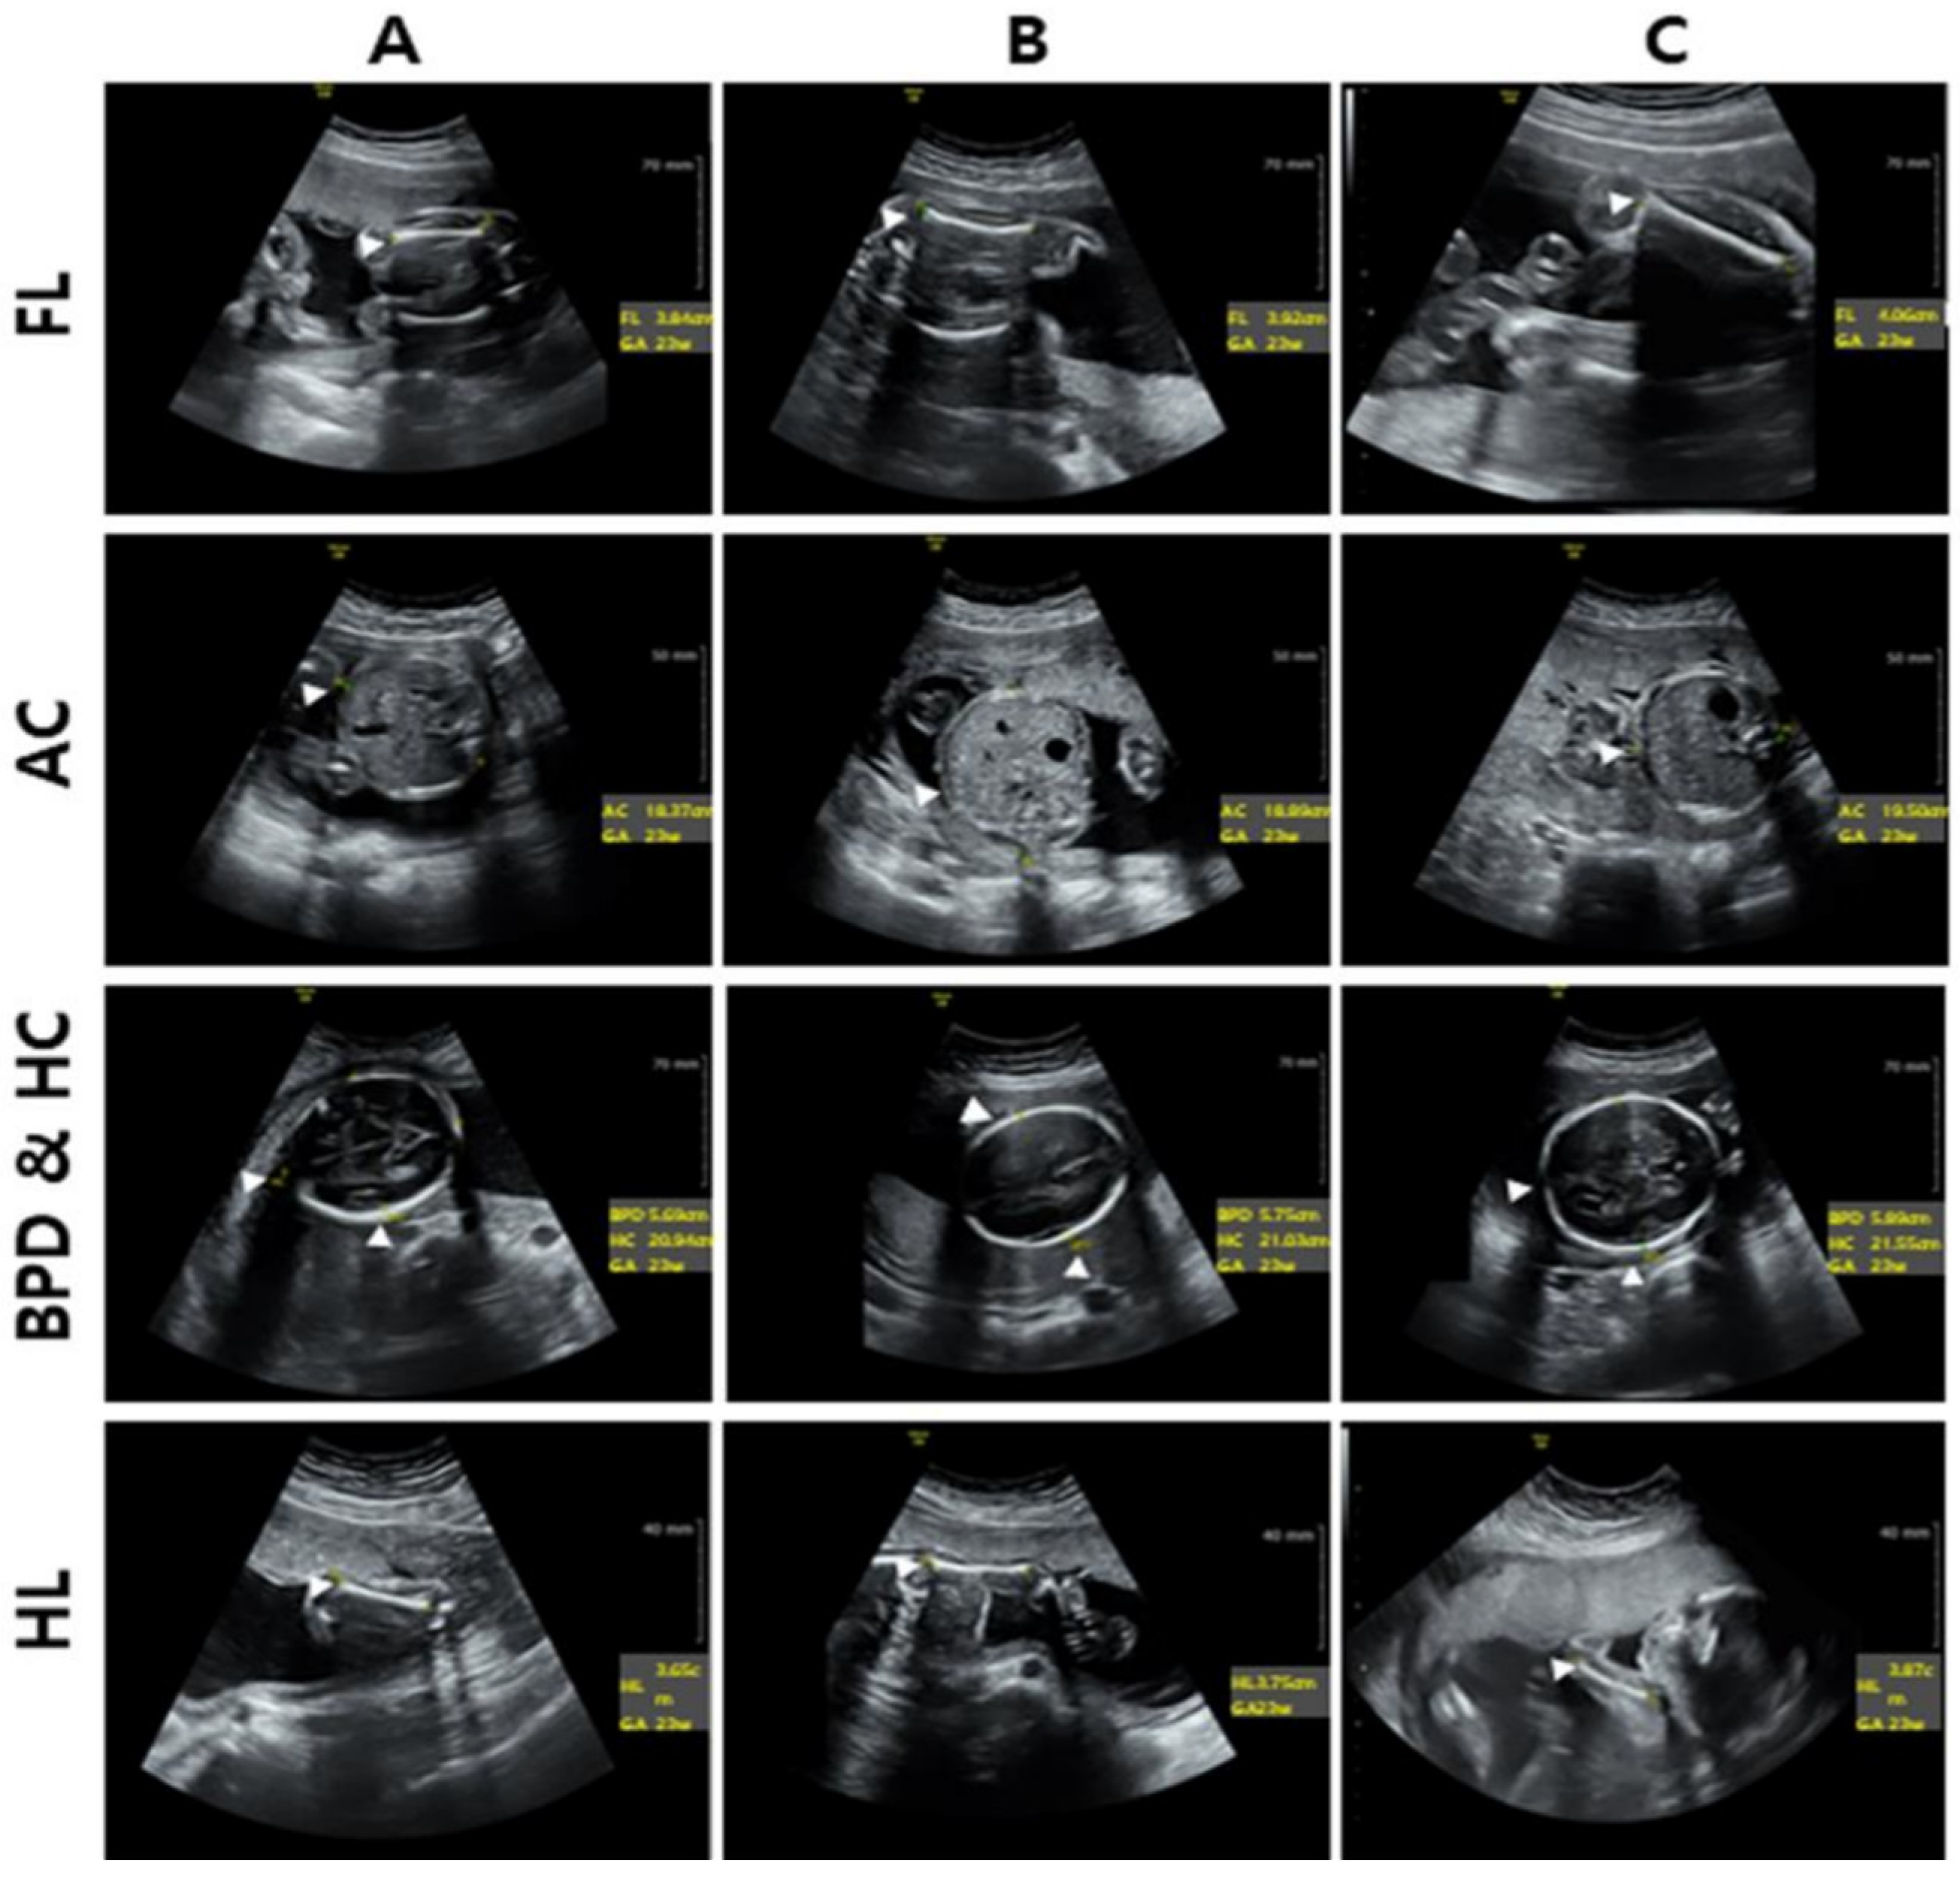

3.6. Results of Prenatal Ultrasonographic Analysis Stratified by Maternal Serum Vitamin D Levels

| Fetus Ultra-Sound Imaging | Vitamin D Group | p-Value | ||

|---|---|---|---|---|

| Deficiency | Insufficiency | Sufficient | ||

| HC | 21.04 (±0.82) | 20.44 (±0.71) | 21.58 (±0.72) | 0.011 |

| AC | 18.56 (±0.92) | 18.37 (±0.76) | 19.08 (±0.70) | 0.11 |

| HL | 3.71 (±0.16) | 3.64 (±0.17) | 3.86 (±0.09) | 0.002 |

| BPD | 5.70 (±0.34) | 5.40 (±0.37) | 5.71 (±0.33) | 0.638 |

| FL | 3.92 (±0.82) | 3.84 (±0.15) | 4.01 (±0.33) | 0.001 |